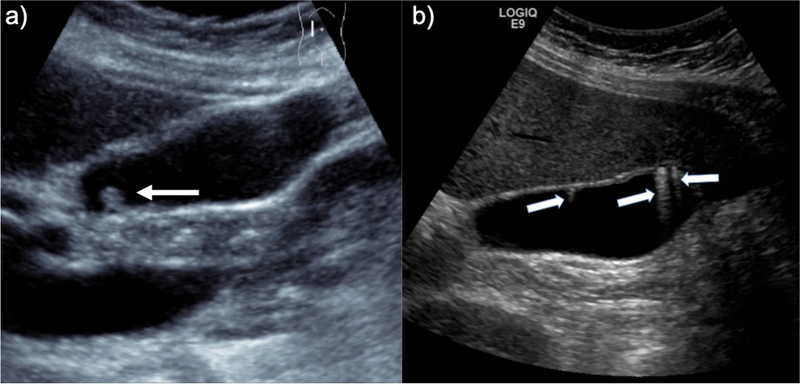

Polyp túi mật là sự phát triển không bình thường của một mảng tế bào lên thành màng niêm mạc bên trong túi mật. Đây là một bệnh lý thường không gây ra triệu chứng và thường được phát hiện trong khi khám sức khỏe tổng quát định kỳ. Polyp túi mật thường được phân loại dựa theo chiều dài và có thể xuất hiện ở nhiều kích thước khác nhau, bao gồm cả kích thước nhỏ như 3mm.

Dù nhỏ bé, polyp túi mật 3mm vẫn có thể chứa một số yếu tố có thể ảnh hưởng đến sức khỏe. Tuy nhiên, polyp túi mật 3mm thường không gây ra bất kỳ triệu chứng gì và chỉ theo dõi thông qua siêu âm để đảm bảo rằng polyp không phát triển lớn hơn hoặc có dấu hiệu bất thường nào.

Bên cạnh việc thăm khám trực tiếp của bác sĩ, để đưa ra được chẩn đoán xác định polyp túi mật 3mm, người bệnh thường được làm các chỉ định cận lâm sàng bao gồm:

Polyp túi mật 3mm thường không đòi hỏi một quá trình quản lý phức tạp. Nếu polyp không gây ra triệu chứng và được xác định không có tính chất bất thường, người bệnh chỉ cần theo dõi tình trạng polyp theo lịch thăm khám và siêu âm định kỳ với bác sĩ. Nếu có triệu chứng đau thượng vị bên phải liên tục, không đỡ cần quay lại bệnh viện thăm khám trực tiếp với bác sĩ. Triệu chứng này có thể cần được theo dõi một cách cẩn thận để xác định có nguy cơ phát sinh các biến chứng nguy hiểm hay không.